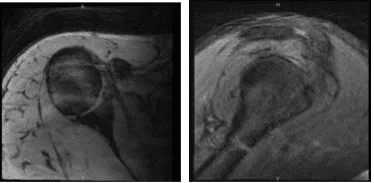

Vino a nuestra consulta con dolor recurrente en el hombro derecho que no ha mejorado. El paciente tenía debilidad en los músculos del manguito rotador. El paciente presentó un resultado de resonancia magnética que mostró que era normal, pero había una alta sospecha de desgarro del manguito rotador.

MRI-3T Hombro derecho sin contraste

Se presentó un resultado de resonancia magnética que mostró tenodesis del bíceps y posible desgarro en el manguito rotador. Evidencia de reparación previa del manguito rotador con ancla de sutura en la tuberosidad mayor. Sin embargo, los hallazgos compatibles con una rotura recurrente del supraespinoso tienen al menos una severidad moderada.

Desgarro parcial de bajo grado del tendón subescapular. Tendinosis y tenosinovitis del bíceps sin desgarros. Hallazgos que sugieren capsulitis adhesiva. Pequeño desgarro en la base del labrum anterior. Bursitis leve.